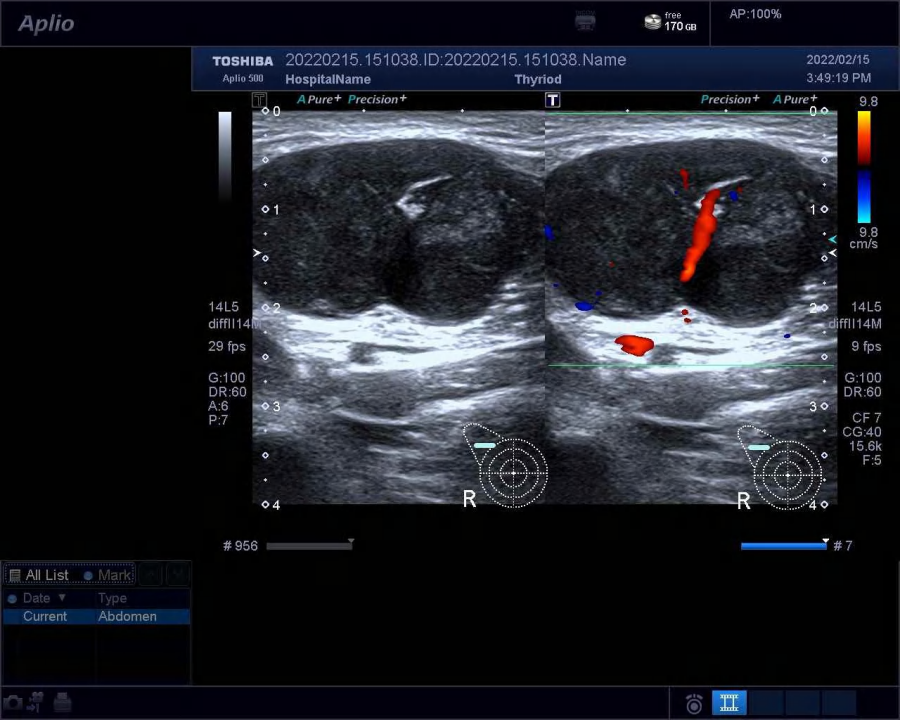

入院行超声检查,可见右手掌背皮下探及一实质性低回声区,范围约 8.1 cm × 3.5 cm × 3.1 cm,与周围组织分界不清,形态不规则,内回声不均,内可见强回声伴声影;

内另见第 3 掌骨骨质破坏、骨皮质连续性中断,内可见低回声区,范围约 3.0 cm × 1.8 cm,边界不清,内回声不均。

CDFI:低回声区内可见稍丰富点棒状血流信号。超声提示:右手掌背皮下不规则低回声区,第 3 掌骨骨质破坏,性质待定,考虑恶性可能,请结合其他检查。

图片图 1 右手背肿物二维超声声像图:不规则实质性低回声,内可见强回声,伴第 3 掌骨骨质破坏

图片图 2 右手背肿物血流信号图:内可见稍丰富点棒状血流信号